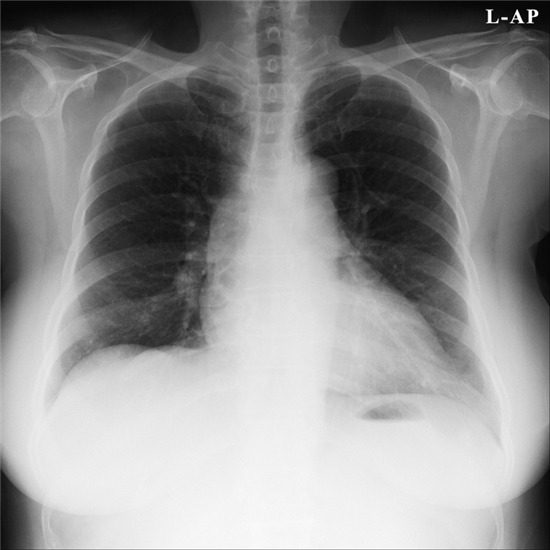

Chest PA사진 보세요.

영상의 차이가 확~ 나시나요???

미세한 Lung Image의 차이... 가끔 실수로 넘기게 되는 경우가 있는데

한번씩 다시  확인을 해야겠네요^^